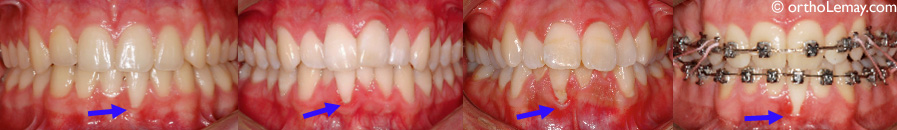

Exemples de différents degrés de récession gingivale sur des incisives inférieures.

Début de récession sur les centrales inférieures causé par l’attache d’un piercing de lèvre chez une femme de 21 ans.